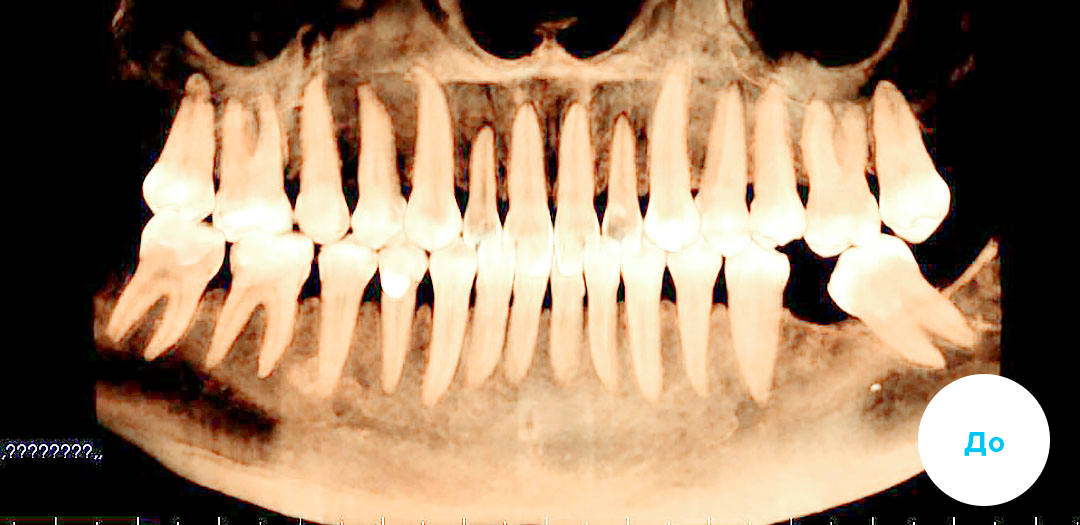

До

После

ИМПЛАНТАЦИЯ 3 ЗУБОВ С ПРЕДВАРИТЕЛЬНОЙ ОРТОДОНТИЧЕСКОЙ ПОДГОТОВКОЙ

Смотреть кейс